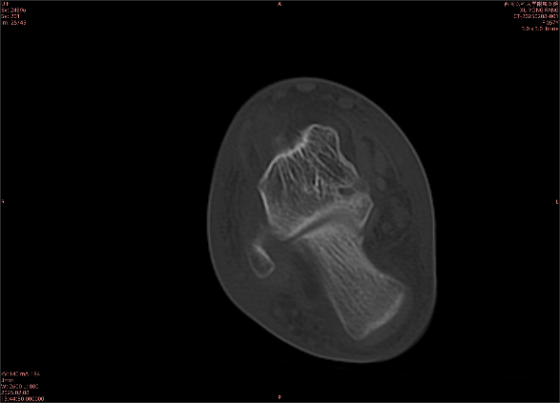

舉例圖像

圖1

專業(yè)解釋看不懂沒關(guān)系,大家看圖1和圖2就可以了,這是同一個患者跟骨的磁共振和CT圖像,圖1的紅色箭頭指示的黑線就是磁共振圖像顯示的骨折線,一目了然。而對比圖2的CT圖像上并未顯示異常。